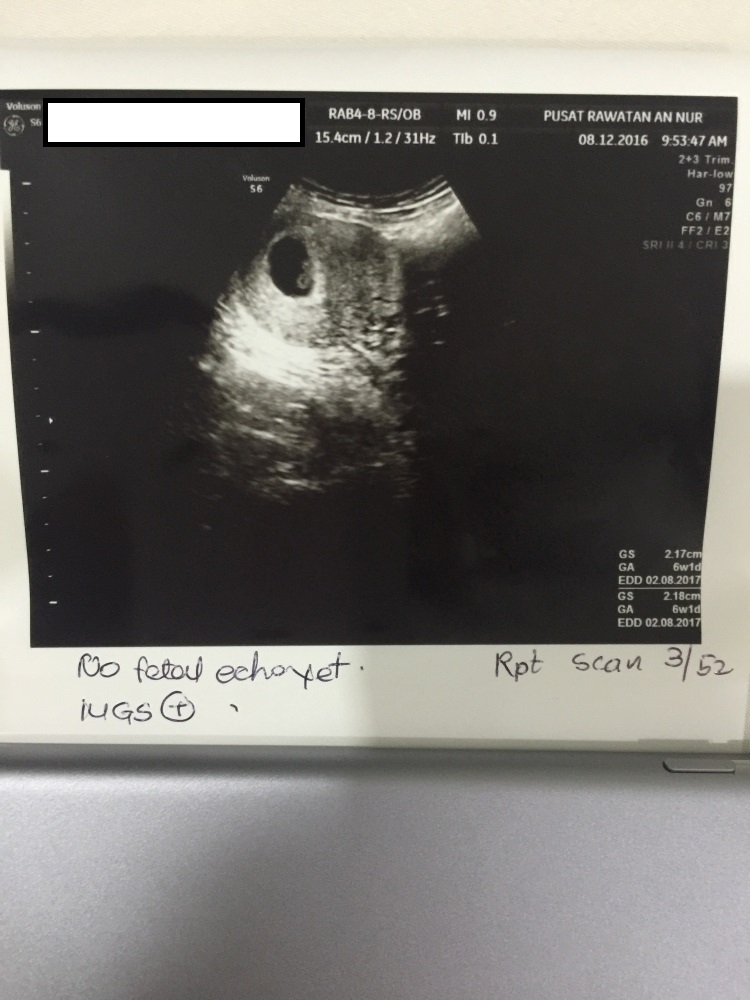

- Scan dibuat pada awalnya di Poliklinik Wahidah pada 1 December

- Kemudian buat lagi scan di Pusat Rawatan An Nur pada minggu berikutnya

- Kemudian buat lagi scan di Pusat Rawatan An Nur pada 22 Dec 2016 (hari ini)

- Total adalah 3 scan

Minggu ke – 6

Minggu ke-6